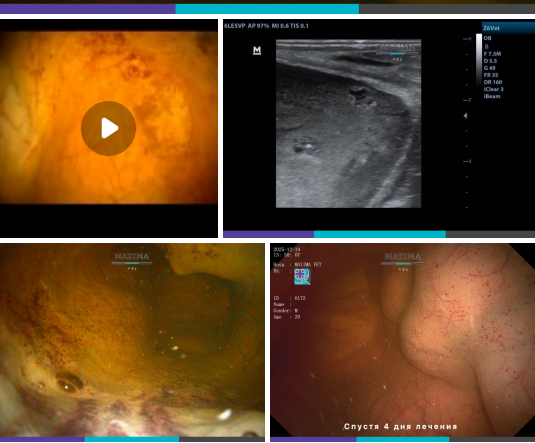

Некоторое время назад такой диагноз у лошадей был редкостью, однако современная ветеринарная медицина шагнула далеко вперед и способна обследовать лошадей гораздо тщательней и подробней, что позволяет обнаруживать признаки данного заболевания на ранних стадиях. Итак, идиопатический геморрагический цистит у лошадей - это воспаление слизистой мочевого пузыря. К наиболее очевидным признакам относятся: частое мочеиспускание, чрезмерная поза при мочеиспускании, кровь в моче или недержание мочи без полного опорожнения (например, мерина часто распускаются и остаются в таком положении, а подтекание мочи происходит в течение дня маленькими дозами). Возможные причины. Обычно возникает вторично по отношению к нарушениям оттока мочи, вызванным: - Бактериальной инфекцией. - Травмой. - Неоплазией (на видео - именно эта причина вызвала данную патологию). - Параличом мочевого пузыря. - Уролитиазом. Диагноз ставится на основании визуальной диагностики (цистоскопии и УЗИ), а также по результатам биопсии

- Неоплазией (на видео - именно эта причина вызвала данную патологию).

Диагноз ставится на основании визуальной диагностики (цистоскопии и УЗИ), а также по результатам биопсии и дополнительных лабораторных исследований.